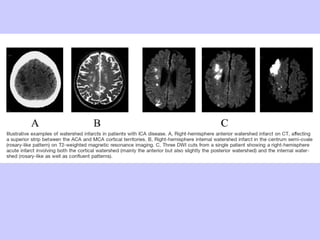

INFARTO WATERSHED CORTICAL